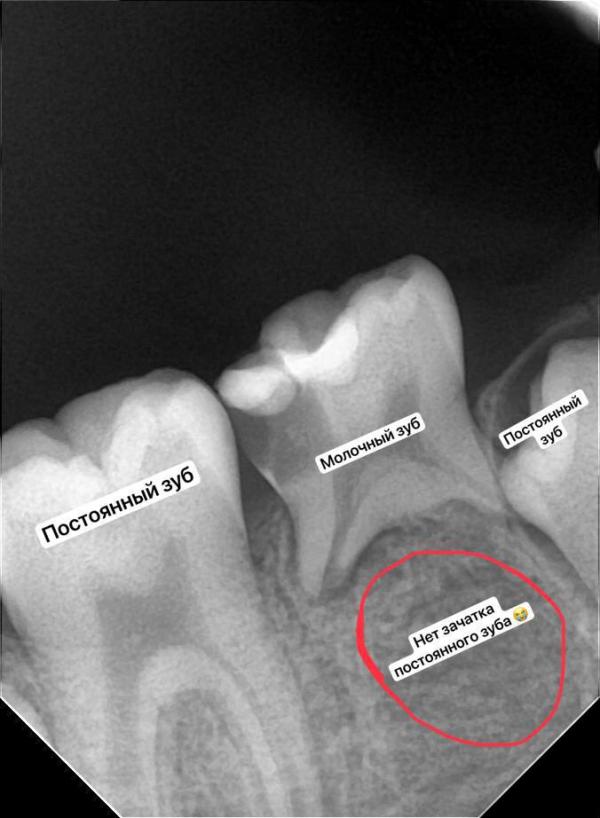

✔️детям могут диагностировать наличие или отсутствие зачатка постоянного зуба, различные аномалии развития.